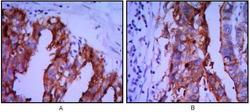

Immunohistochemistry

OAAD00366 IHC

Full details

Method: